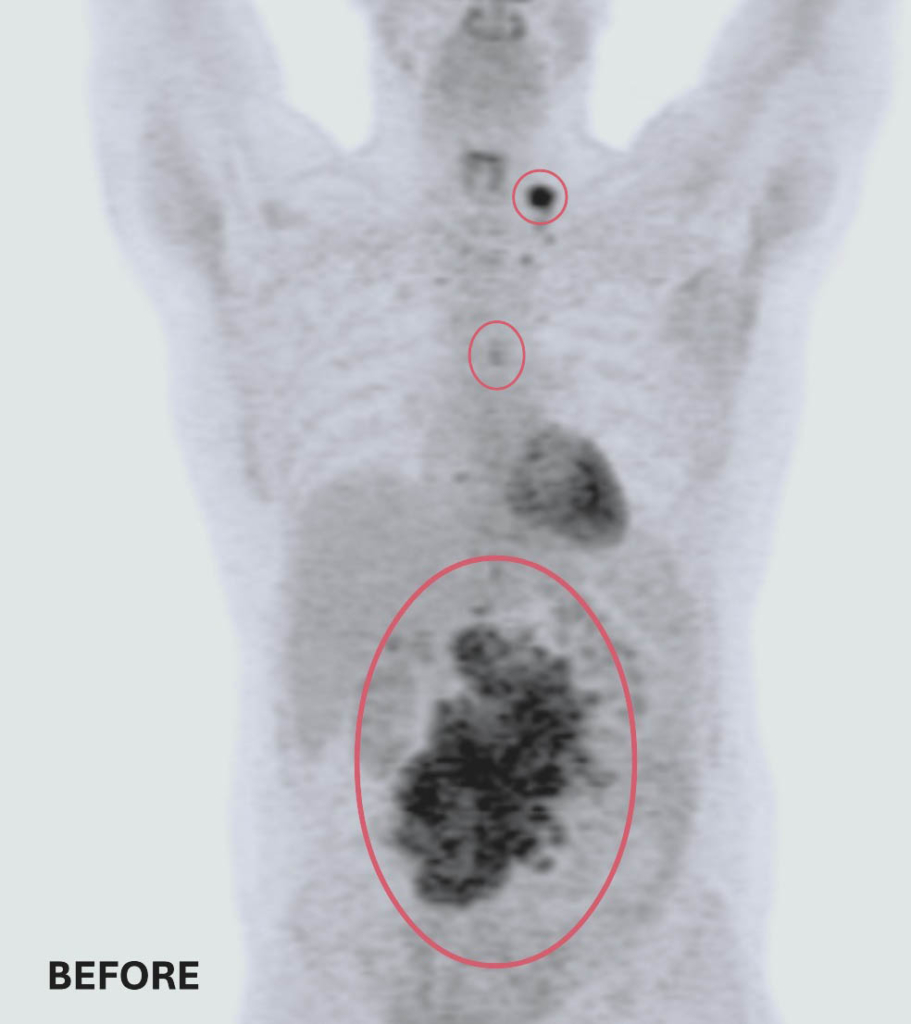

Une TEP révèle la présence de trois tumeurs. La plus grande et la plus préoccupante se trouve dans l’abdomen et mesure 14 cm x 14 cm x 9 cm – environ la taille et la forme d’une très grosse patate douce. Les deux autres sont près de son œsophage et de sa clavicule.

Clichés d’imagerie médicale avant et après ses traitements : deux des trois tumeurs de Ted ont complétement disparu. La troisième est maintenant de la taille d’un petit pois – Ted répond très bien au traitement suivi à L’Hôpital d’Ottawa.